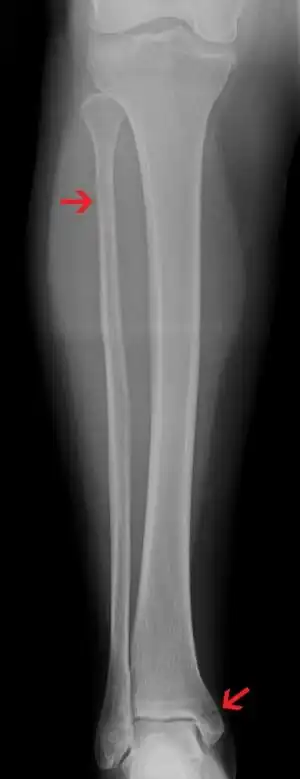

| A Maisonneuve fracture with arrows marking the location of the two fractures | |